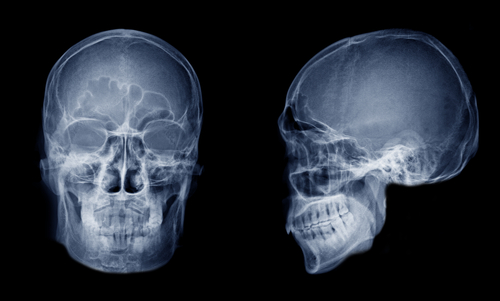

- Позиционирование. Голову фиксируют так, чтобы луч прошел строго через интересующую область. Чаще всего выполняют стандартный набор, куда входит и рентген пазух носа 2 проекции (подбородочно-носовая и затылочно-подбородочная). При сложных случаях добавляют боковой ракурс и позицию с открытым ртом.

Результаты рентгенографии околоносовых придаточных пазух

Врач анализирует снимок последовательно: сначала изучает норму, затем ищет отклонения.

Нормальная картина:

- Лобный и верхнечелюстной синусы выглядят как симметричные воздушные треугольники с ровными костными стенками.

- Решетчатый лабиринт содержит тонкие перегородки, а клиновидная полость занимает центральное положение.

- Контуры прозрачны, уровней жидкости нет, слизистая не утолщена.

Типичные патологические находки:

- Горизонтальный уровень жидкости. Свидетельствует об остром гнойном гайморите либо фронтите; важно срочно назначать антибактериальную терапию.

- Диффузное затемнение синуса. Чаще всего указывает на кисту, полипозное разрастание или грибковое поражение; без КТ уточнить границы образования сложно.

- Утолщение костной стенки, нарушение контура. Возможный признак хронического воспаления, доброкачественной остеомы или малигнизации.

- Смещенные фрагменты кости. Диагностируются при свежем или давнем переломе, требуют консультации челюстно-лицевого хирурга.

- Рентген-плотная тень в газовой полости. Может означать инородное тело; решение о хирургическом удалении принимают после осмотра ЛОР-врача.

Благодаря такому анализу рентген околоносовых пазух носа позволяет уточнить диагноз, выбрать метод лечения, а затем контролировать динамику без избыточной лучевой нагрузки. При необходимости второй рентген пазух носа спустя 7–10 дней показывает, насколько эффективно работает назначенная схема терапии.